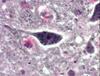

what is pictured

autonomic ganglia